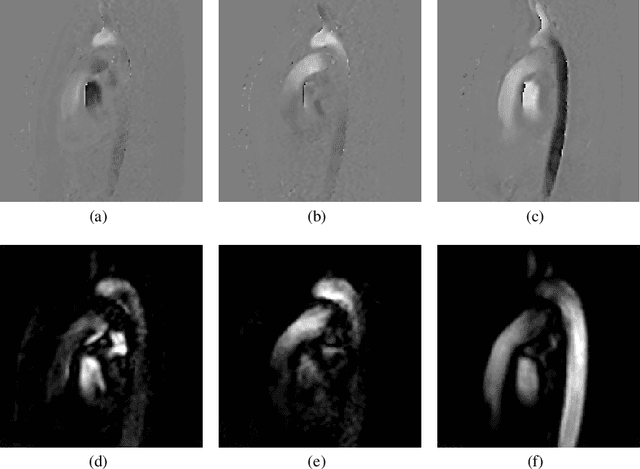

Abstract:An accurate assessment of the cardiovascular system and prediction of cardiovascular diseases (CVDs) are crucial. Measured cardiac blood flow data provide insights about patient-specific hemodynamics, where many specialized techniques have been developed for the visual exploration of such data sets to better understand the influence of morphological and hemodynamic conditions on CVDs. However, there is a lack of machine learning approaches techniques that allow a feature-based classification of heart-healthy people and patients with CVDs.In this work, we investigate the potential of morphological and hemodynamic characteristics, extracted from measured blood flow data in the aorta, for the classification of heart-healthy volunteers and patients with bicuspid aortic valve (BAV). Furthermore, we research if there are characteristic features to classify male and female as well as younger and older heart-healthy volunteers. We propose a data analysis pipeline for the classification of the cardiac status, encompassing feature selection, model training and hyperparameter tuning. In our experiments, we use several feature selection methods and classification algorithms to train separate models for the healthy subgroups and BAV patients. We report on classification performance and investigate the predictive power of morphological and hemodynamic features with regard to the classification oft he defined groups. Finally, we identify the key features for the best models.

Abstract:Morphology of cardiovascular tissue is influenced by the unsteady behavior of the blood flow and vice versa. Therefore, the pathogenesis of several cardiovascular diseases is directly affected by the blood-flow dynamics. Understanding flow behavior is of vital importance to understand the cardiovascular system and potentially harbors a considerable value for both diagnosis and risk assessment. The analysis of hemodynamic characteristics involves qualitative and quantitative inspection of the blood-flow field. Visualization plays an important role in the qualitative exploration, as well as the definition of relevant quantitative measures and its validation. There are two main approaches to obtain information about the blood flow: simulation by computational fluid dynamics, and in-vivo measurements. Although research on blood flow simulation has been performed for decades, many open problems remain concerning accuracy and patient-specific solutions. Possibilities for real measurement of blood flow have recently increased considerably by new developments in magnetic resonance imaging which enable the acquisition of 3D quantitative measurements of blood-flow velocity fields. This chapter presents the visualization challenges for both simulation and real measurements of unsteady blood-flow fields.